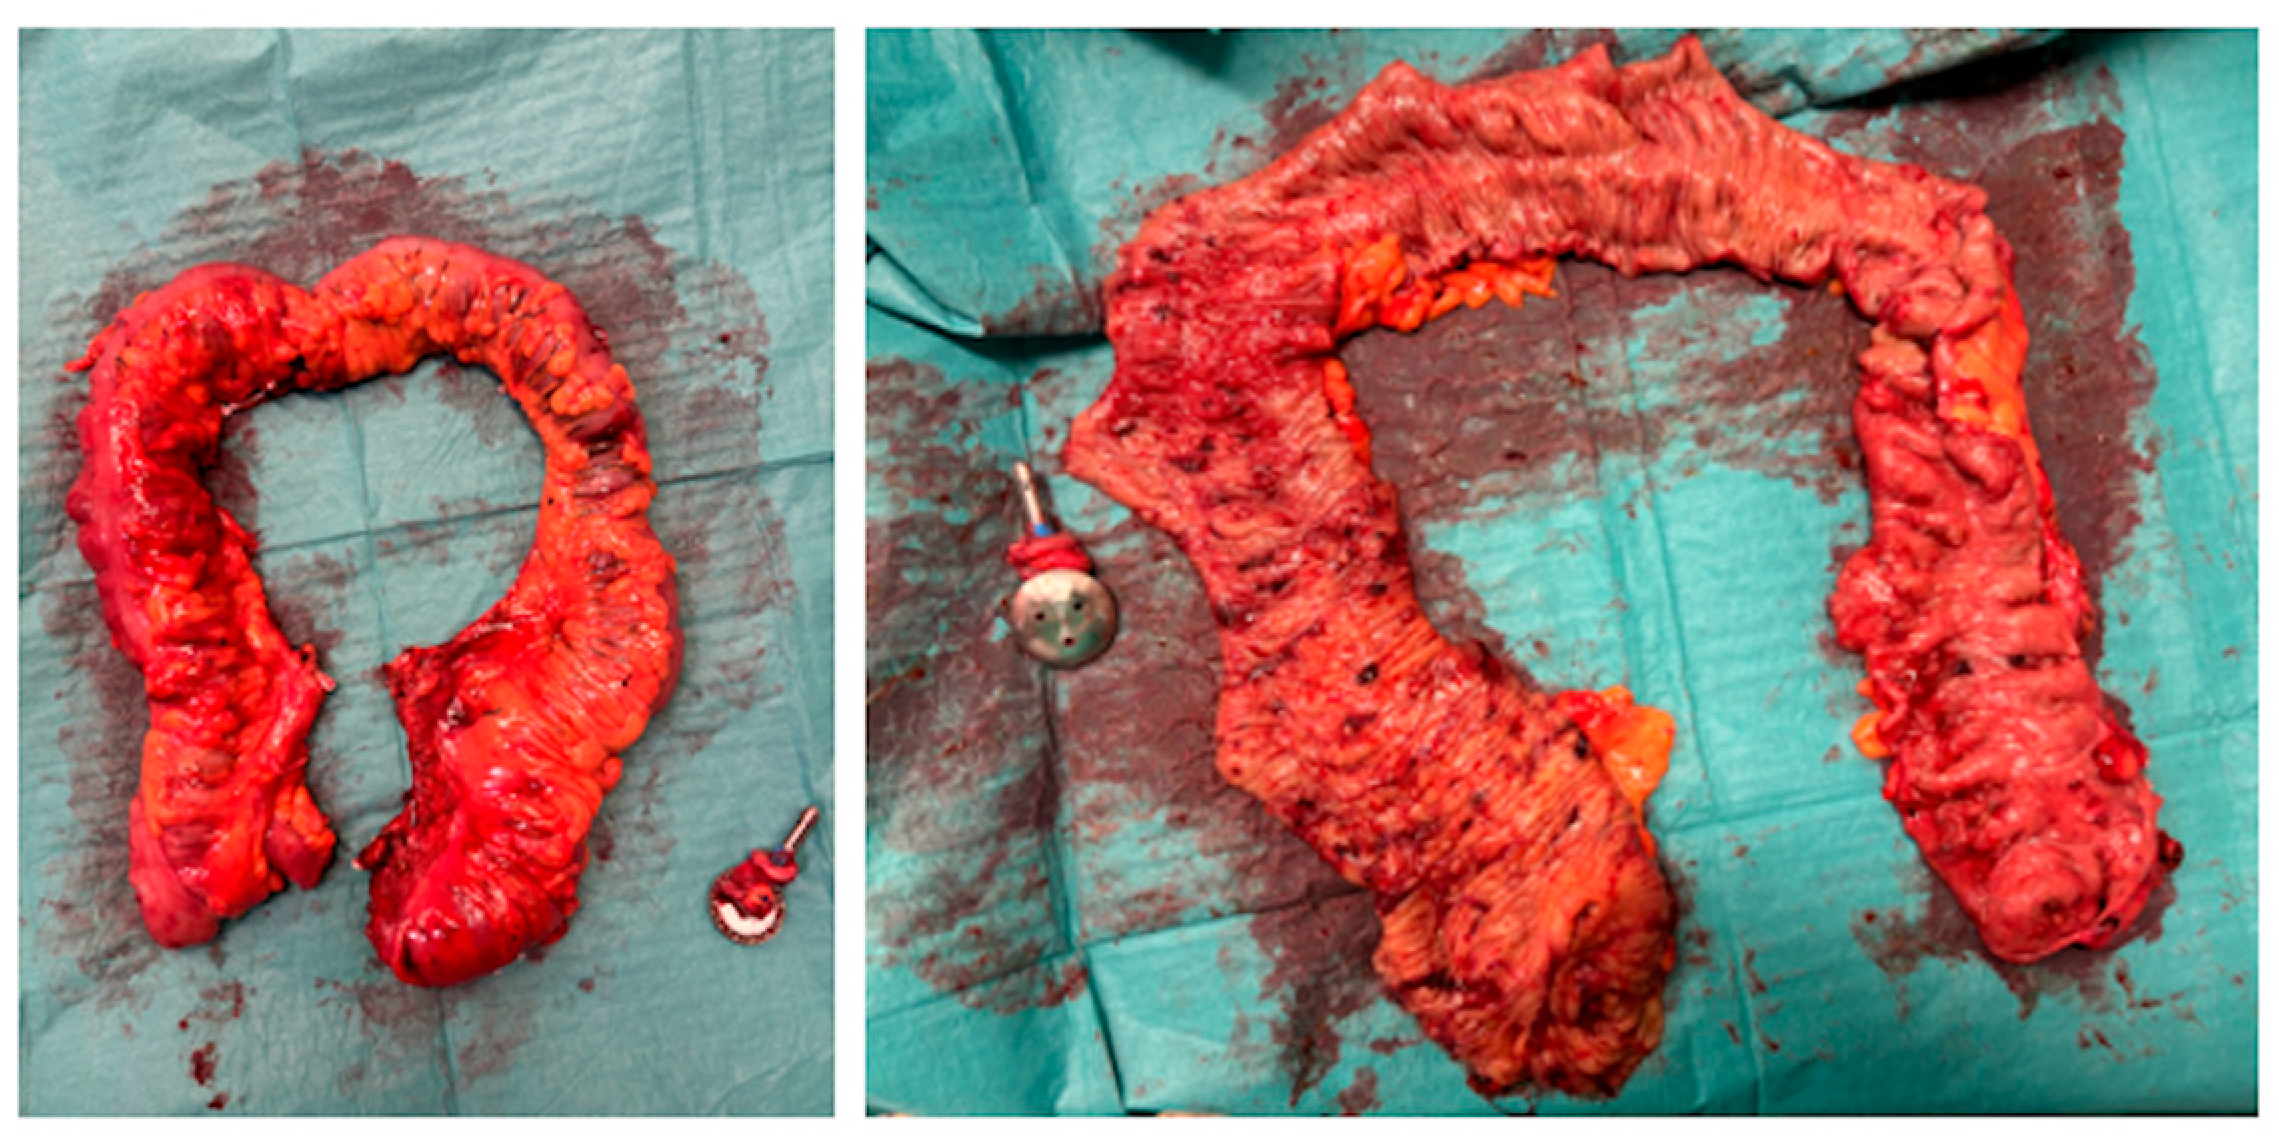

- A.

- Suprapubic incision;

- B.

- Extraction of the surgical specimen;

- C.

- Ileorectal anastomosis.

| Phase V Laparoscopic Assisted Phase | N/A | - Suprapubic (Pfannenstiel) incision | - Removal of robotic trocars; - Use of traditional laparoscopic instruments. | - Incision for extraction of surgical specimen; - Division of the ileum and introduction of a 28 mm EEA circular stapler anvil; - Transanal ileorectal anastomosis; - Integrity test of the anastomosis with methylene blue; - Closure of the ports. |